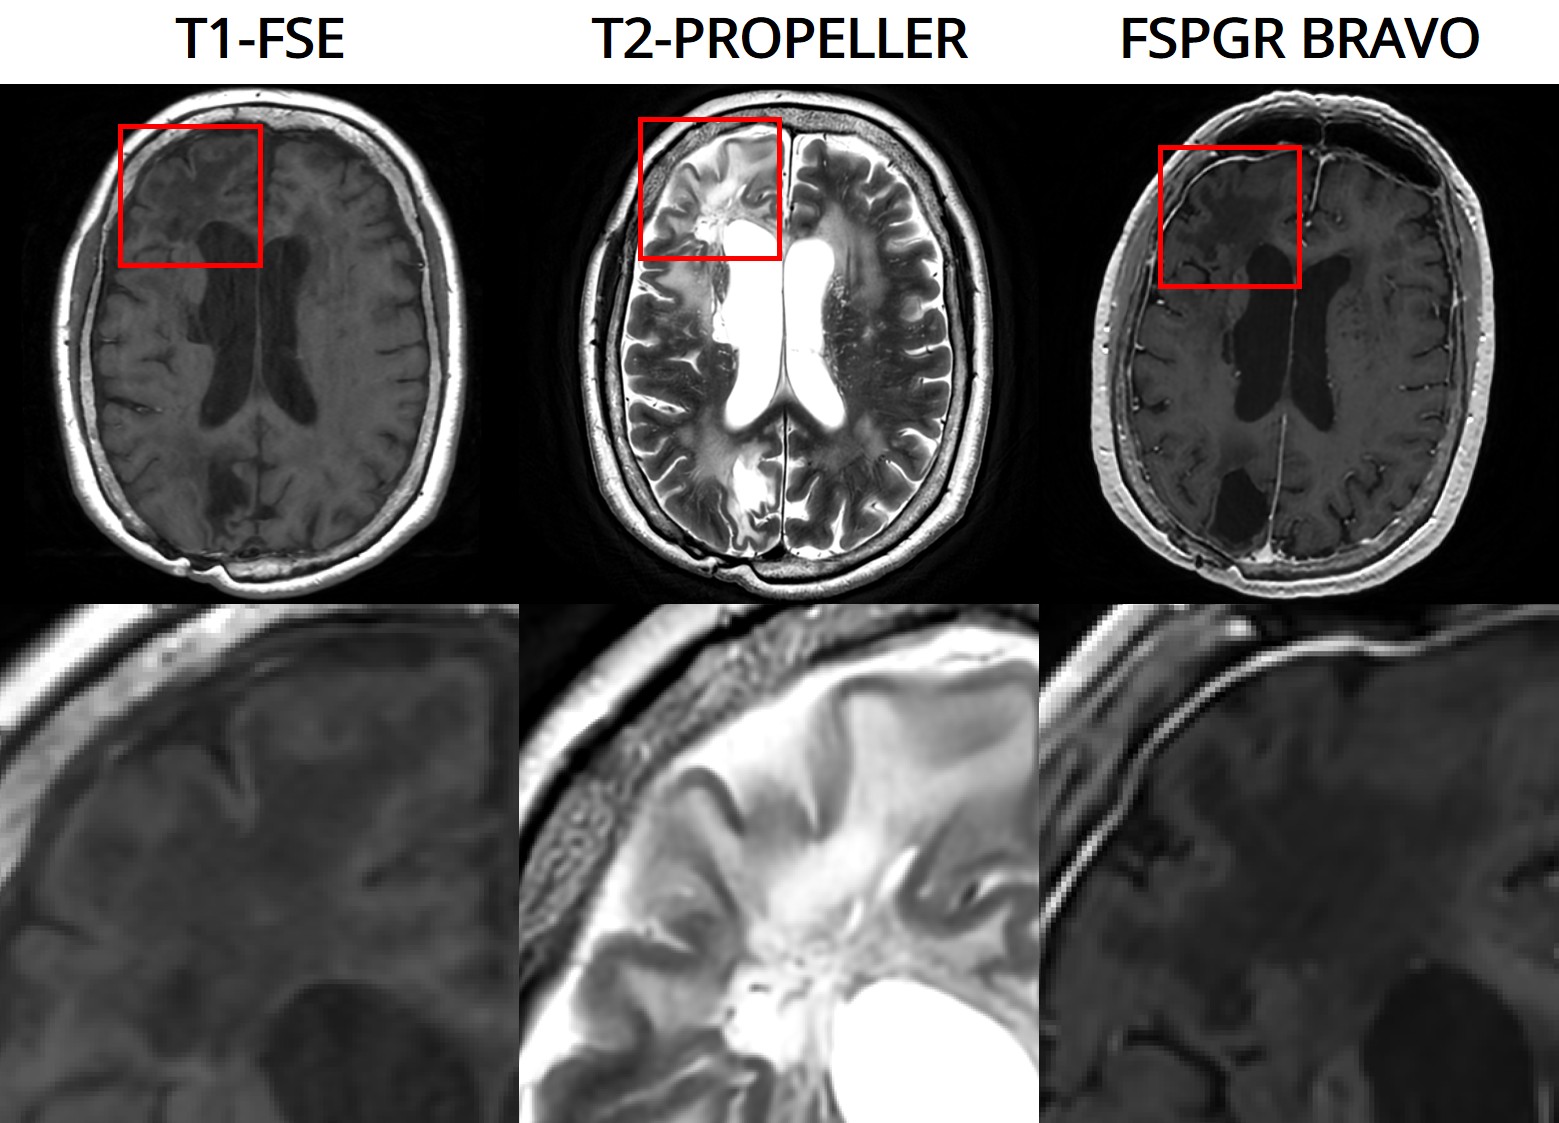

The 3D fast silent multi-parametric mapping sequence with zero echo time (MuPa-ZTE) is a novel quantitative MRI (qMRI) acquisition that enables nearly silent scanning by using a 3D phyllotaxis sampling scheme. MuPa-ZTE improves patient comfort and motion robustness, and generates quantitative maps of T1, T2, and proton density using the acquired weighted image series. In this work, we propose a diffusion model-based qMRI mapping method that leverages both a deep generative model and physics-based data consistency to further improve the mapping performance. Furthermore, our method enables additional acquisition acceleration, allowing high-quality qMRI mapping from a fourfold-accelerated MuPa-ZTE scan (approximately 1 minute). Specifically, we trained a denoising diffusion probabilistic model (DDPM) to map MuPa-ZTE image series to qMRI maps, and we incorporated the MuPa-ZTE forward signal model as an explicit data consistency (DC) constraint during inference. We compared our mapping method against a baseline dictionary matching approach and a purely data-driven diffusion model. The diffusion models were trained entirely on synthetic data generated from digital brain phantoms, eliminating the need for large real-scan datasets. We evaluated on synthetic data, a NISM/ISMRM phantom, healthy volunteers, and a patient with brain metastases. The results demonstrated that our method produces 3D qMRI maps with high accuracy, reduced noise and better preservation of structural details. Notably, it generalised well to real scans despite training on synthetic data alone. The combination of the MuPa-ZTE acquisition and our physics-informed diffusion model is termed q3-MuPa, a quick, quiet, and quantitative multi-parametric mapping framework, and our findings highlight its strong clinical potential.💡 Summary & Analysis